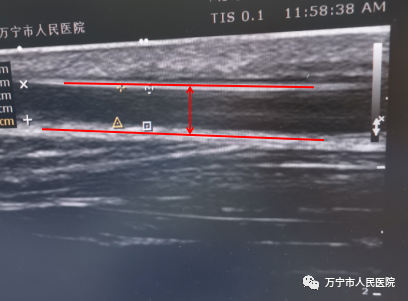

术前血管狭窄(内径0.18cm)—红色线条区间

在完善对动静脉内瘘的相关检查中发现,动静脉内瘘静脉流出道距吻合口约5cm处内瘘杂音高调、震颤减弱,彩超检查发现此处存在5cm狭窄长度、内径宽度仅为0.18cm,在评估患者病情并取得患者同意后,决定为患者进行“超声引导下动静脉内瘘球囊扩张术”治疗狭窄问题,治疗后狭窄处内径改善,彩超下内径宽度变为0.289cm,透析时血流量可达280ml/min,能提供充足的血流量维持充分透析,达到治疗目的。

术后血管通畅(内径0.289cm)—红色线条区间